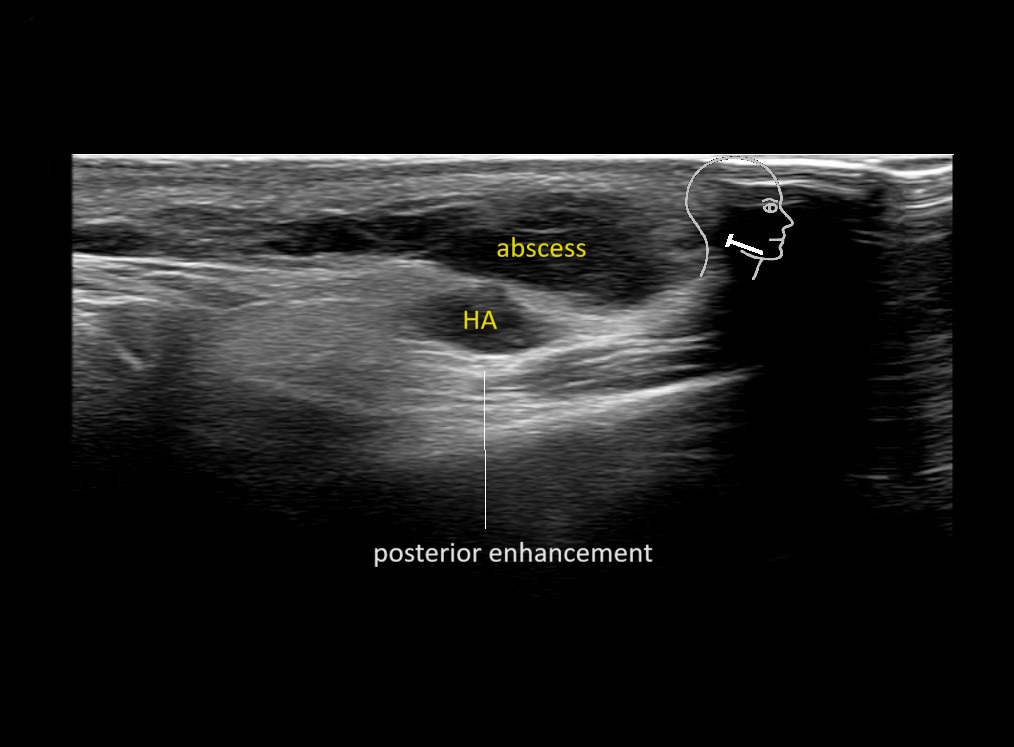

Filler injections in the parotid gland may go unnoticed, however, inflammatory reactions and abscesses may occur. Hypervascularity can be seen with color doppler. Filler deposits are supposed to be injected into the superficial fatty layer . The space to inject into this layer may be limited. Routinely we measure a width of 2-4 millimeters with sometimes subcutaneous layers being less than one millimeter thick.

Study the first image to recognize the different layers. If you are sure about the layers, swipe to the second image to view the answer (if applicable).